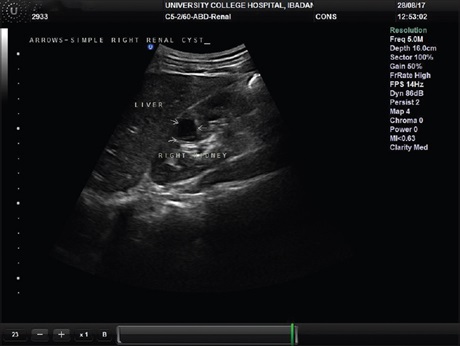

Nutcracker syndrome presenting as recurrent hematuria

Dr. Blessing Ose‑Emenim Igbinedion, Festus Oghanina Ehigiamusoe, Stanley Ngoka (Author)

127-131